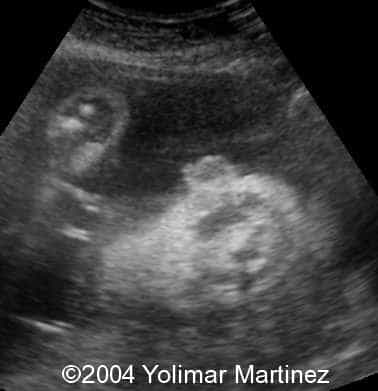

The single nostril

Imagen 40

Imagen4